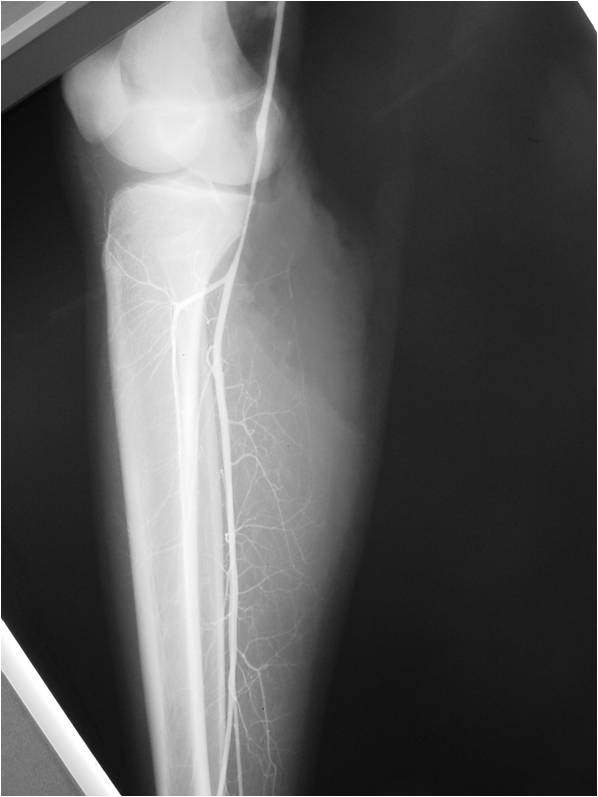

Radiographic Presentation

- Aggressive motheaten to permeative lesion

- Indistinct border in most cases

- Osseous destruction with a soft tissue component

- Chondroid matrix calcification may be present (60-70% of cases)

- Soft tissue mass